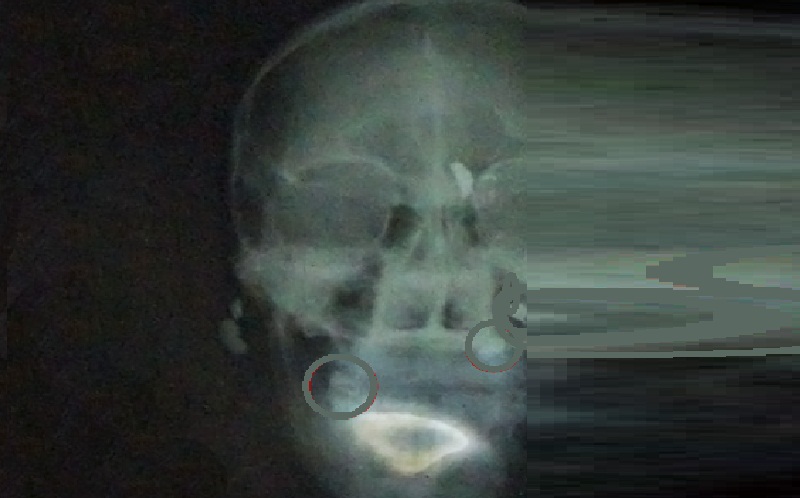

Um projétil atravessou a cabeça da vítima, que deve ter alta em breve.(Foto:Ilustrativa)

A vítima A.G.M.C de 25 anos foi atendido na emergência do Hospital Municipal onde foi constatada que a bala atravessou a cabeça, segundo hospital ele não corre risco de morte, esta sob observação médica.

De acordo com o hospital, a bala afetou a parte subcutânea da pele e não atingiram nenhum osso nem o cérebro, ele teve muita sorte”, completa.